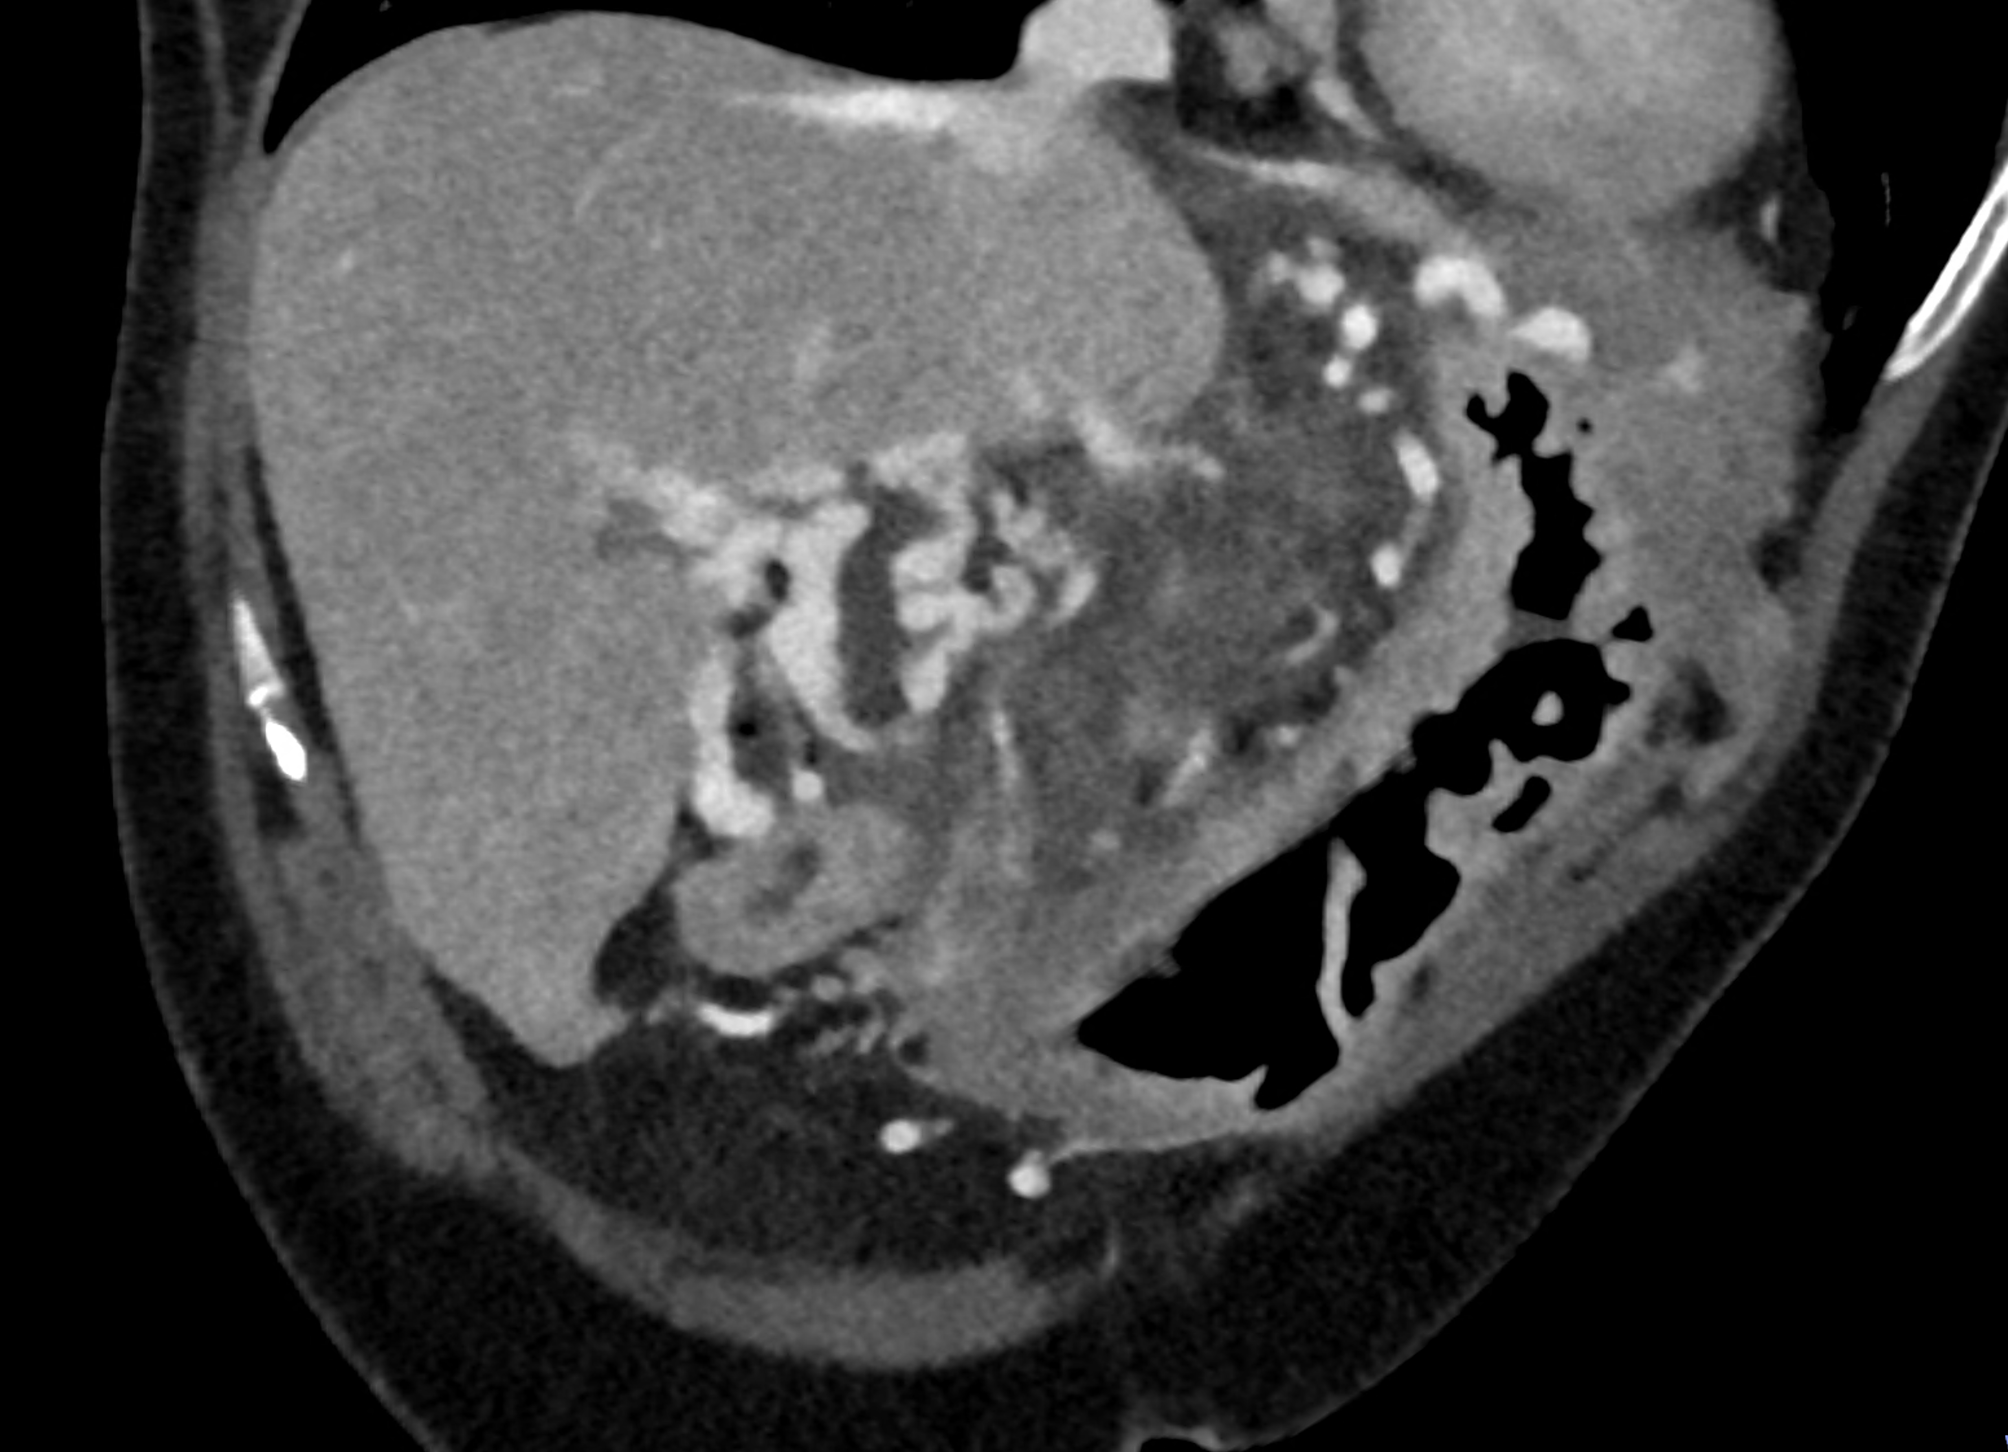

During CT, the most significant phase is the portal phase of liver enhancement, when portal biliopathy is associated with dilation of the bile duct wall, which is significantly enhanced with the contrast agent in the case of dilation of the epicholedochal plexus, or there is a combination with varicose veins around the saturated bile duct wall (dilatation of the paracholedochal plexus). Other possibilities include enhancement of only the paracholedochal plexus and a combination of dilatation of the paracholedochal plexus with cavernous remodelling of the portal vein itself.

The spectral characteristics of data obtained using photon-counting CT allow optimization of the signal from the venous system, thereby increasing the difference between saturated collaterals and the surrounding area. At the same time, excellent spatial resolution aids in the visualization of bile ducts filled with bile.

A patient with chronic pancreatitis and chronically occluded portal vein. The bile ducts have a significantly dilated wall, from the trunk, through the stump of the cystic duct, to the right and especially the left branch of the hepatic duct. At the same time, a large pseudocyst in the pancreas, dilatation of the pancreatic duct, and chromic occlusion of the superior mesenteric vein, splenic vein, and portal vein trunk are evident. Along with portal biliopathy, there is also arixy of the cardia and esophagus, as well as cavernous remodeling of the portal circulation itself.

dilated veins in the wall of left hepatic duct

dilated veins in the wall of left hepatic duct and paralel veins of portal cavernous transformation

dilated veins in the wall of cystic duct

dilated collaterals in hepatoduodenal ligament partially portal biliopathy, partially cavernous transformation

dilated veins in the wall of common hepatic duct

reconstruction paralel to hepatoduodenal ligamant